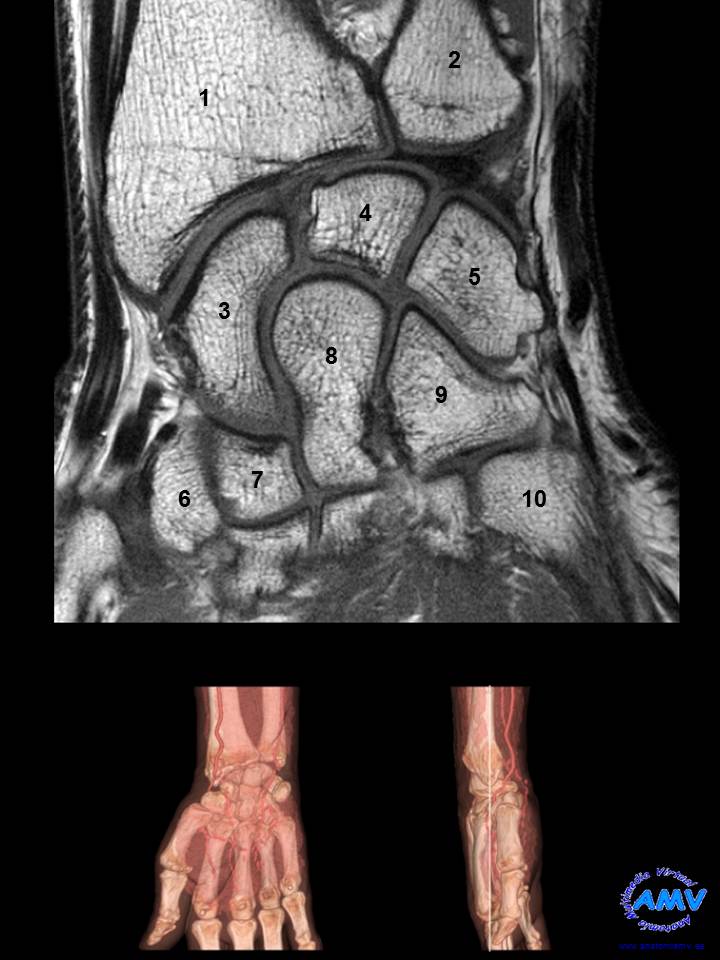

RMN Coronal de Muñeca

ms_rmn_10.jpgIndique que estructura se señala con el número correspondiente:

El nº 1 señala al hueso .

El nº 2 señala al hueso .

El nº 3 señala al hueso .

El nº 4 señala al hueso .

El nº 5 señala al hueso .

El nº 6 señala al hueso .

El nº 7 señala al hueso .

El nº 8 señala al hueso .

El nº 9 señala al hueso .

El nº 10 señala a la base del .